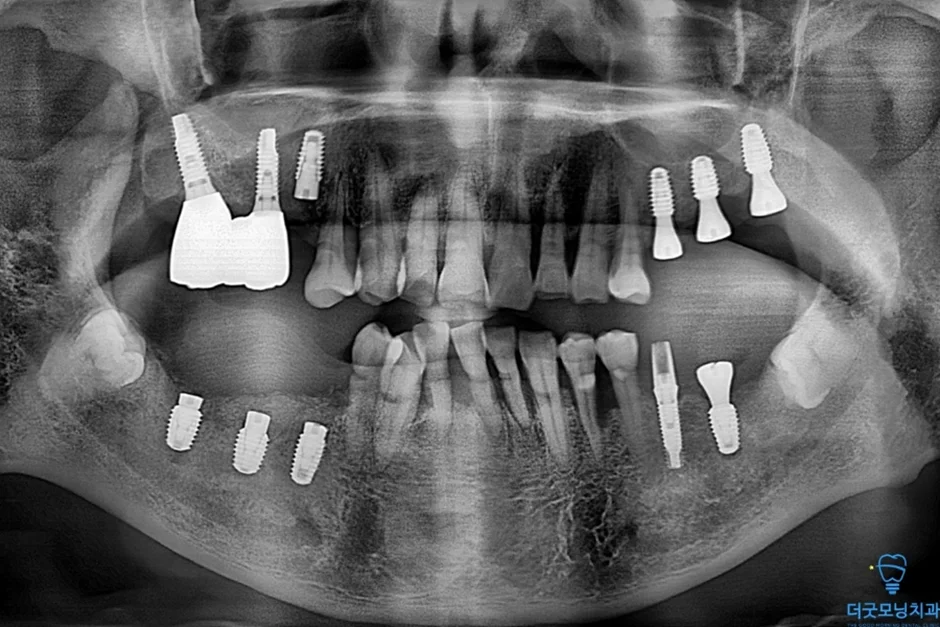

■ 2차 수술 (왼쪽)

환자분이 충분히 회복하신 이후 반대쪽도 동일하게 수면치료로 진행하였습니다.

노란색 표시처럼 임플란트 식립 잘 마쳤습니다.

두 번째 수술에서도 임플란트가 CT 상에서 확인될 만큼 정확하고 안정적으로 식립되었습니다.

■ 보철 마무리

양쪽 임플란트 식립이 완료된 후 보철 준비를 거쳐 최종 보철까지 마무리하였습니다.